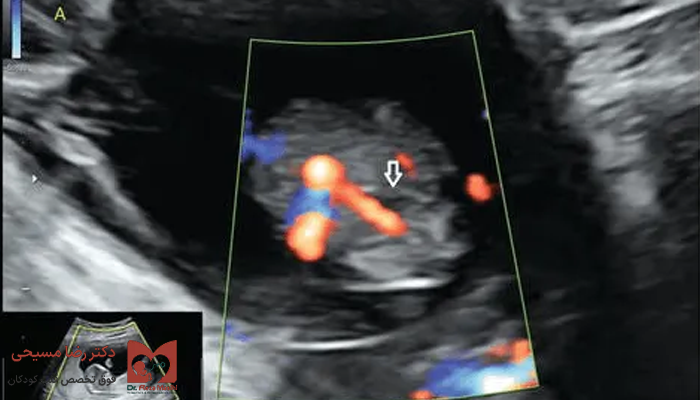

این سونوگرافی تخصصی، عملکرد قلب جنین رو با جزئیات زیاد بررسی میکند. چون در بعضی موارد، بند ناف تک شریانی با مشکلاتی در قلب یا سایر اندامهای جنین همراه است.

- جریان خون: بررسی مسیر ورود و خروج خون در قلب

- عروق اصلی قلب: بررسی شریان ریوی و آئورت و مسیر صحیح آنها